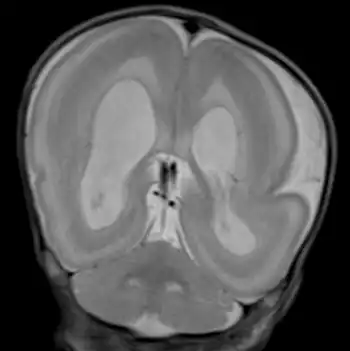

Visuals of the brain

The brain is usually grossly abnormal in outline when someone is diagnosed with Miller–Dieker syndrome. Only a few shallow sulci and shallow Sylvian fissures are seen; this takes on an hourglass or figure-8 appearance on the axial imaging. The thickness and measurement for a person without MDS is 3–4 mm. With MDS, a person's cortex is measured at 12–20 mm.

With the use of prenatal ultrasonographic imaging, early detection of abnormal brain development in the fetus with MDS can be seen. At birth, facial dysmorphism can be present in the infant. Young children, when affected, can have feeding difficulties, severe intellectual disability, developmental delay, and seizures. MRI facilitates early detection of this syndrome in children by revealing a "smooth brain" image, also called lissencephaly.[7] Children with this syndrome may remain underdiagnosed because of rarity and the prevalence of facial features that appear to be dysmorphic. The syndrome shares distinct external features (phenotype) similar to more common syndromes. Lack of relevant family history may delay diagnosis. FDNA provides a service that in turn increases the chances of detecting these distinct characteristics, which, when shown to a geneticist, can assist in reaching the right medical diagnosis. If a couple has had one child with MDS, they can be offered prenatal screening in future pregnancies. This option is particularly important for the 20% of MDS families where one parent carries a balanced chromosome rearrangement. The risk of these couples having another child with MDS depends on the exact type of chromosomal rearrangement present and may be as high as 25–33%. For families in which both parents' chromosomes are normal, the risk of having another child with MDS is low (1% or less). Either chorionic villus sampling (CVS) or amniocentesis can be used early in a pregnancy to obtain a small sample of cells from the developing embryo for chromosome studies. Early prenatal diagnosis by ultrasound is not reliable because the brain is normally smooth until later in pregnancy. Couples who are considering prenatal diagnosis should discuss the risks and benefits of this type of testing with a geneticist or genetic counselor.

MDS was named for the two physicians, James Q. Miller[8] and H. Dieker.,[9] who independently described the condition in the 1960s. The hallmark of MDS is lissencephaly, a condition in which the outer layer of the brain, the cerebral cortex, is abnormally thick and lacks the normal convolutions (gyri). In some areas of the brain, gyri are fewer in number but wider than normal (pachygyri). Other areas lack gyri entirely (agyri). Normally, during the third and fourth months of pregnancy, the brain cells in the baby multiply and move to the surface of the brain to form the cortex. Lissencephaly is caused by a failure of this nerve cell migration. MDS is often called Miller-Dieker lissencephaly syndrome.